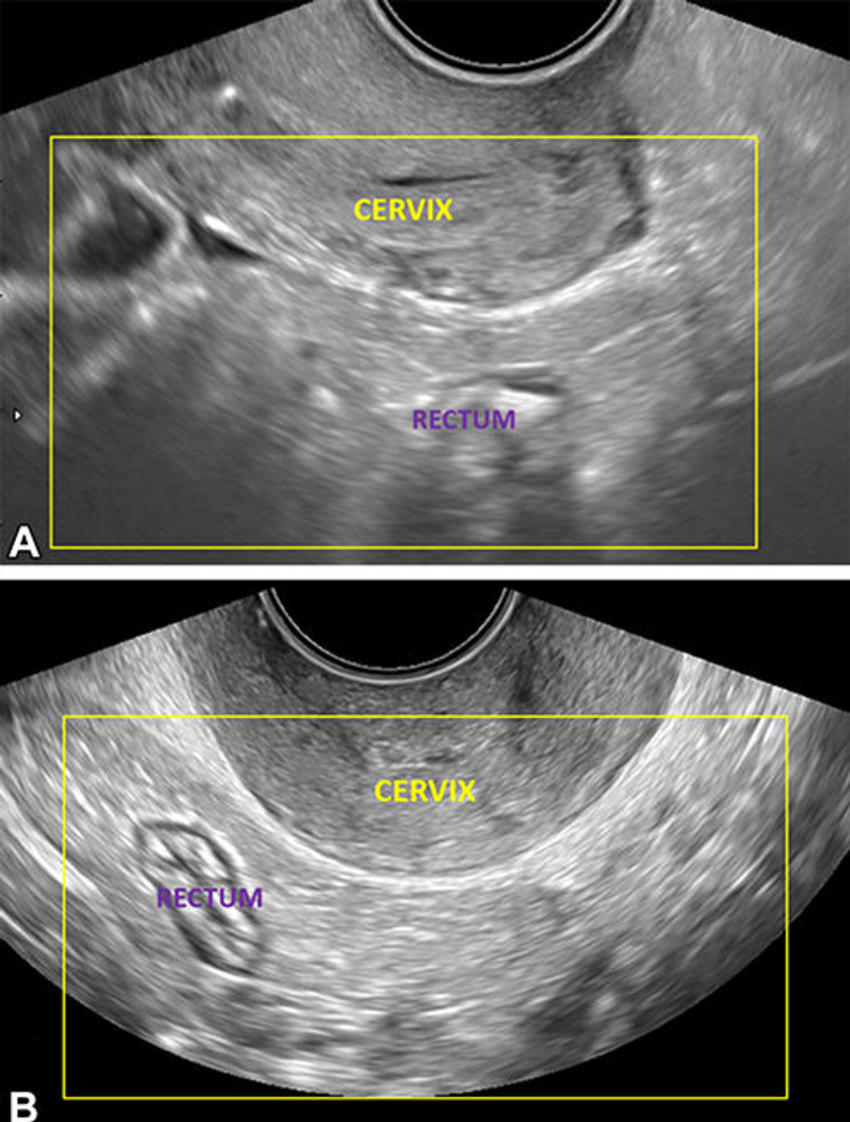

Figure 1. Transvaginal US images show the posterior compartment in a 25-year-old patient with dysmenorrhea, on the retrocervical field of view (area of interest outlined in yellow), 4–5-cm deep to the cervix. Longitudinal (A) and transverse (B) views. The transducer is in the anterior fornix. Longitudinal and transverse sweeps were acquired to include these areas.